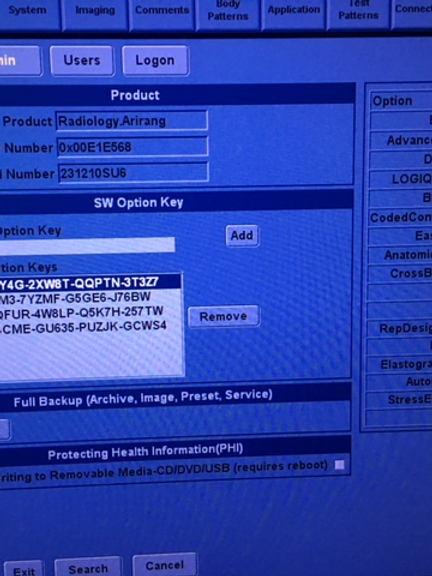

Feature-Rich Performance: Enjoy access to premium features typically found on more expensive devices, including CrossXBeam composite imaging, cardiac imaging, and speckle reduction. The LOGIQ P5 sets a new standard for affordability without compromising on performance.

Effortless Optimization: Streamline your workflow with automatic tissue optimization, coded harmonic imaging, and high pulse repetition rate capabilities. The LOGIQ P5 is designed to enhance efficiency and accuracy, empowering healthcare professionals to focus on patient care.

- Premium features including CrossXBeam composite imaging and cardiac imaging

- Automatic tissue optimization and coded harmonic imaging for enhanced image quality